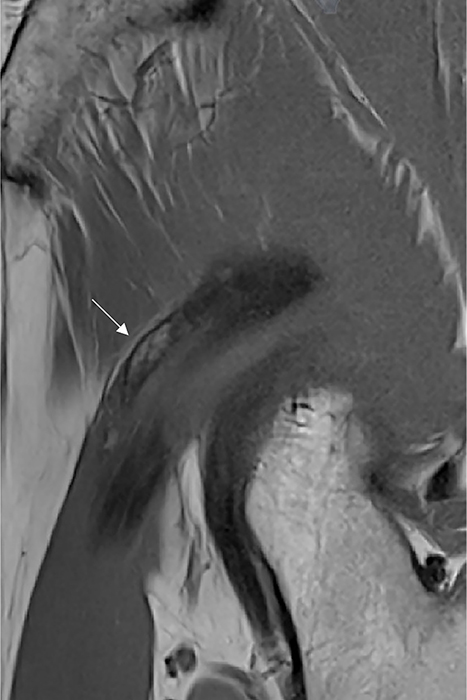

Figure 2

Magnetic Resonance Imaging shows mature HO containing fatty bone marrow along the course of the indirect head of the rectus femoris (arrow) on sagittal T1‑weighted images.